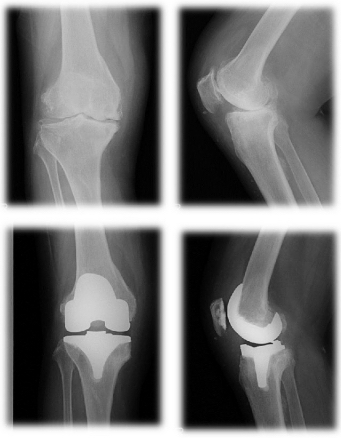

「長く歩けなくなった」「立ち座りが辛い」。高齢社会の日本では、膝に不安を持つ人は1千万人にものぼるといわれています。今回は、変形性膝関節症の患者さんが対象となる人工膝関節置換術の治療法について説明していきます。

人工膝関節置換術は年間約8万件行われている手術で、手術の対象となるのは、関節の間にある軟骨や半月板がすり減ったり、変形することで痛みや機能障害を招く変形性膝関節症と診断された方々です。もともと骨の形がO脚の人や、若い時のケガが原因になることもありますが、一番は老化、使いすぎです。高齢者に多いのはこのためで、筋力が落ちてきたり、体重が増えることで症状が深刻になってきます。

人工膝関節置換術の内容は、傷ついてしまった膝の軟骨や骨を表面的に切り取り、膝の変形を矯正し、金属やセラミック、ポリエチレンなどでできた人工関節に置き換える手術です。手術は1時間程度で終わります。膝がとても痛くて、変形性膝関節症の方やリウマチの方が手術の適応になります。